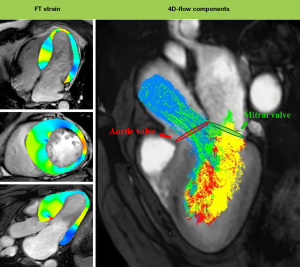

CMR tissue tracking analysis

CMR tissue tracking analysis was performed in the FT module. The endocardial and epicardial LV borders at end diastole were semiautomatically delineated with manual adjustment on cine images. The contours were automatically tracked throughout the cardiac cycle and manually corrected to ensure accurate boundary tracking. The strains were computed at each myocardial point, covering the whole myocardium on each section. The number of myocardial points corresponds to that of pixels between the endocardial and epicardial contours. The global peak systolic strain for the LV in all three directions was obtained by averaging the values from the myocardial points (Figure 2).

Analysis of LV flow components

Analysis was performed using a method previously validated by Eriksson (18). Briefly, the software identified the mitral and aortic valve positions on the three-chamber cine sequence to define the boundaries for estimating LV flow parameters. After confirming the valve positions, the software options were selected to match them to the segmented geometric model, with manual adjustments made to the position and size of the mitral and aortic valves when necessary to achieve automatic image registration between the cine and velocity magnitude images. Pathlines were emitted from the center of each voxel and tracked both forward and backward to cover systole and diastole. The ventricular blood particles were automatically separated by the pathlines into four distinct blood flow components, including (I) direct flow (DF): blood that enters the LV during diastole and leaves during systole within the same cardiac cycle; (II) retained inflow (RIF): blood that enters the LV during diastole but is not ejected during systole within the same cardiac cycle; (III) delayed ejection flow (DEF): blood that is already in the LV at the beginning of diastole and is ejected during systole; and (IV) residual volume (RV): blood that remains within the LV for at least two consecutive cardiac cycles (19,20) (Figure 2). A more detailed description is provided in Appendix 1.